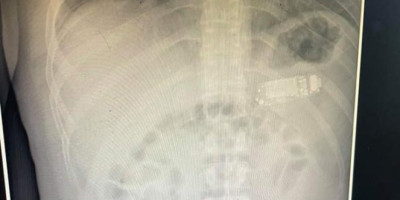

Scena kao u filmovima desila se na Gastroenterološkoj klinici u Prištini. Lekari nisu mogli da veruju slici koju je pokazivao ultrazvuk - u stomaku mladića videli su mobilni telefon! Kako je navedeno, mladić je u bolnicu došao 4 dana nakon što je progutao uređaj.

Lekar Skender Teljaku predvodio je medicinski tim tokom zahvata, rekavši da su prvo izvukli maske sa telefona iz trbuha, a zatim i bateriju, koja se smatra najopasnijim delom.

- Osoba koja je progutala strano telo, morala je hitno na gastroskopiju. Kada smo ušli u stomak videli smo da je telefon podeljen na tri dela. Jedan deo je bio plastični prednji i zadnji poklopac, plus baterija unutra. Ušli smo opremom koju imamo. Na kraju smo izvadili bateriju, koja je od svih ovih delova najopasnija jer je taj deo ozračen i mogao je da eksplodira u crevima, da oslobodi hemikalije - rekao je doktor.

Kako je ispričao, zahvat vađenja telefona je trajao dva sata, a pacijentu nije presecan stomak.